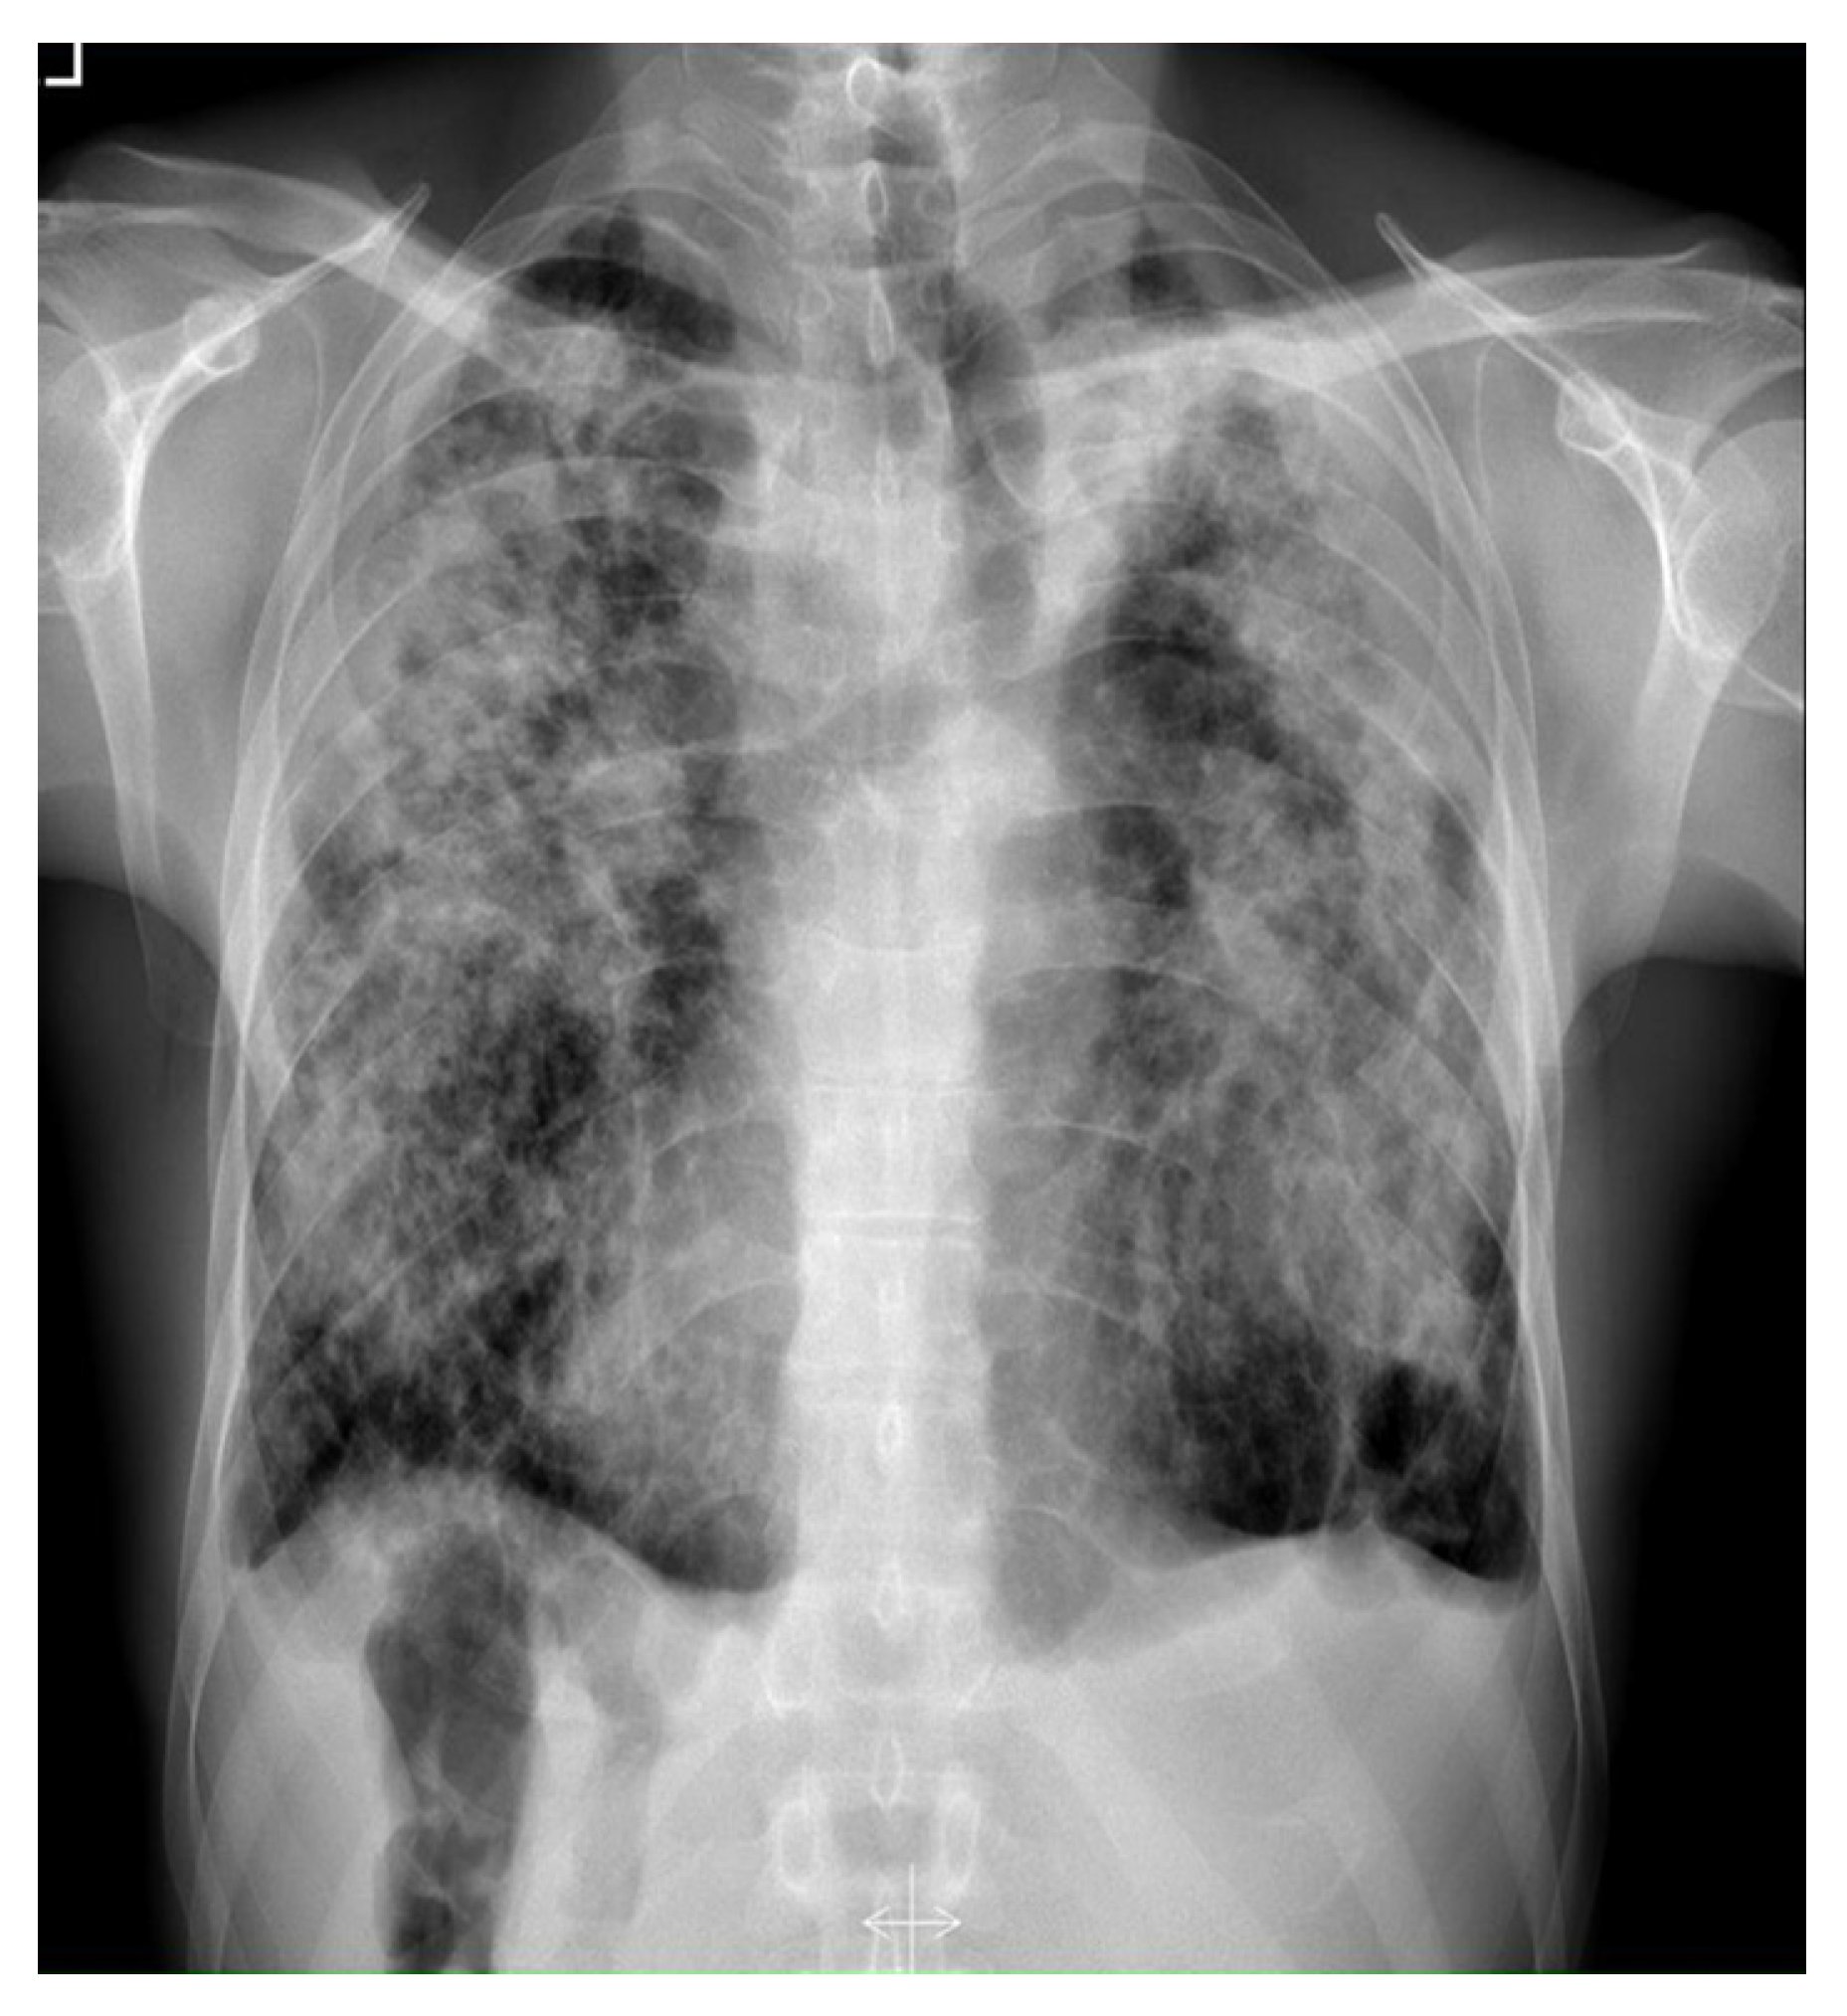

| Radiologic presentation (any of the following) | X-ray: nodular or cavitary lesions |

| HRCT: bronchiectasis and nodular opacities | |